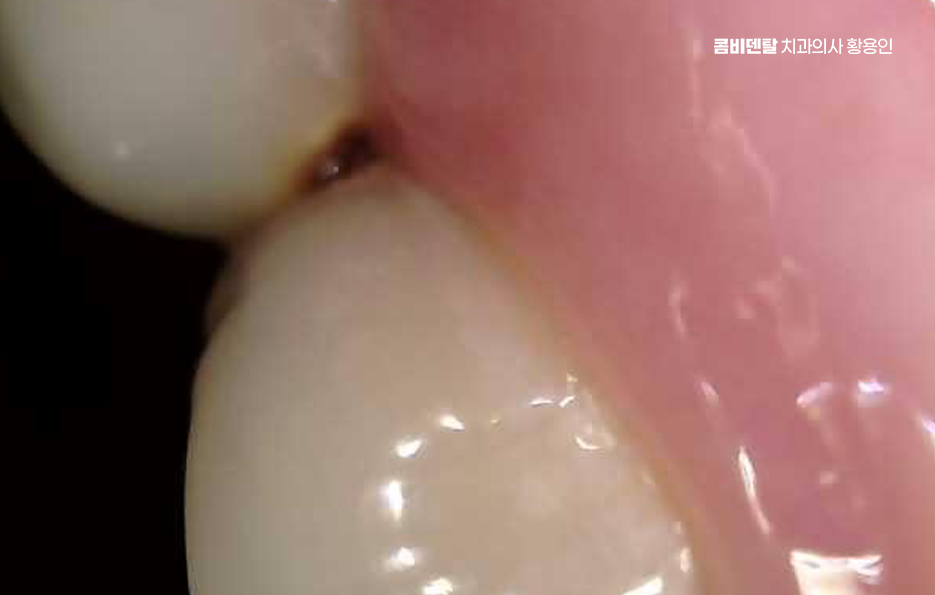

특히 밤에 통증이 심해진다거나, 차가운 물만 닿아도 벌컥 쏘시는 느낌이 있다면 이미 신경에 염증이 깊이 들어간 신경이 감염되어 염증이 진행중일 가능성이 높고 이럴 때는 신경을 제거하고 근관을 소독해서 통증을 줄이는 방식으로 치료를 진행하게 되는 거예요.

신경치료 아픈가요에 대한 궁금증과 두려움을 갖는 분들이 워낙 많을 정도로 통증이 무서워서 치료를 미루는 경우도 많은데 사실 신경치료를 미룰수록 치아 내부 압력이 높아지고, 세균이 더 깊숙이 침투하게 되며 이럴 경우 단순한 치료로는 해결되지 않고 발치로 이어지거나 심한 경우 잇몸 뼈에도 문제가 깊어질 수 있어요